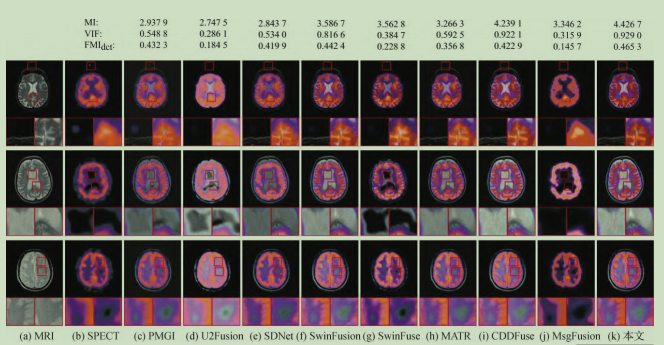

本文方法与其他8种方法在MRI和SPECT图像上的比较: